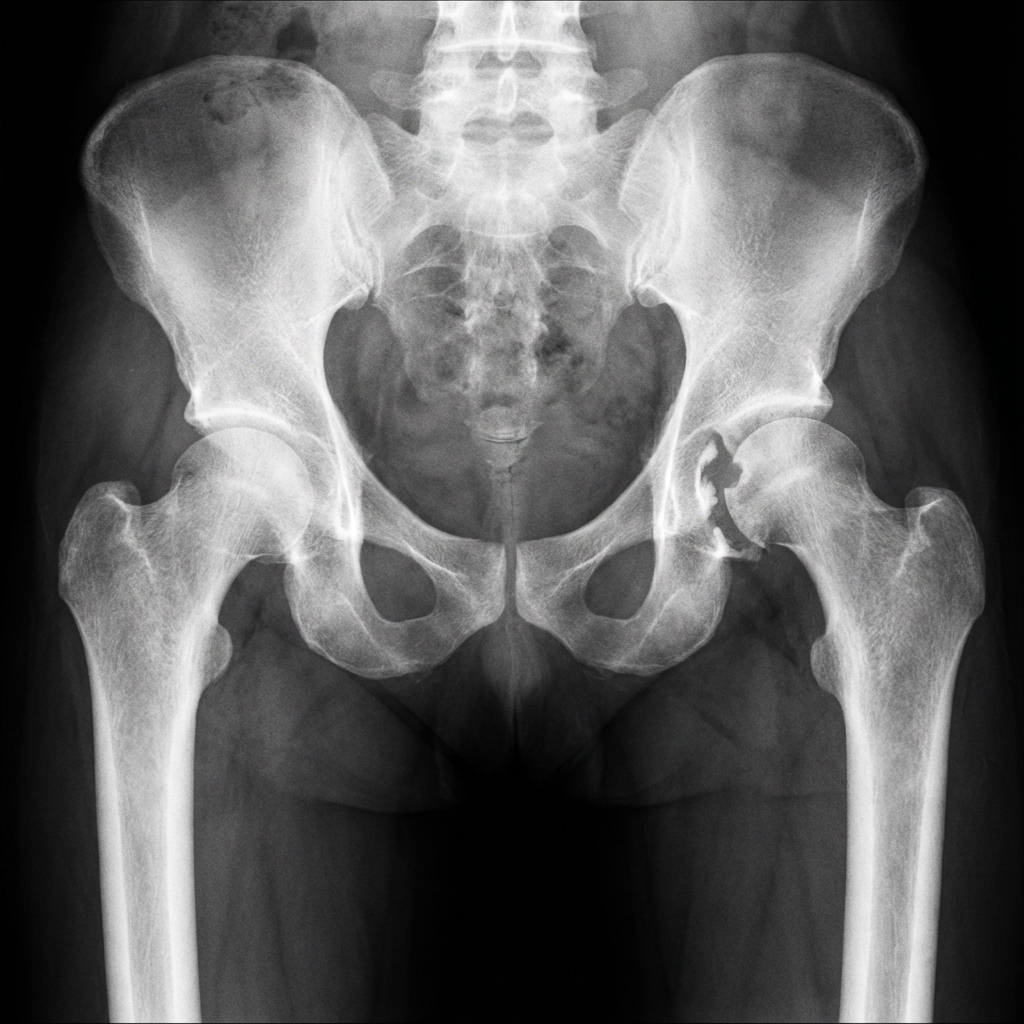

AP pelvis showing posterior wall acetabular fracture with associated posterior hip dislocation. The femoral head is displaced posteriorly with loss of Shenton's line. Obturator oblique view demonstrates posterior wall fragment size. CT shows >40% wall involvement with marginal impaction.

Image source: Open Access medical literature (NIH/PubMed Central) • CC-BY License